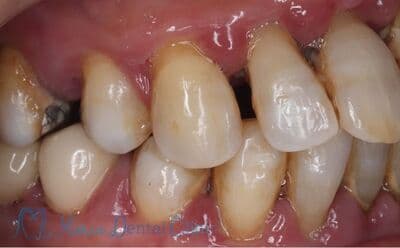

重度の歯周病

歯周病によって骨の喪失が著しく、歯が縦に揺れている状態。

本症例の患者様は、右側の歯を抜歯した後そのまま放置していたことで噛み合わせが大きく乱れ、右上の歯周病が進行して抜歯に至りました。抜歯後は上顎洞に近接して骨量が著しく不足していたため、サイナスリフトによって新たな骨を増やし、インプラントを支える土台を再建しました。十分な骨量を確保することで、奥歯の咬合支持を回復した症例です。